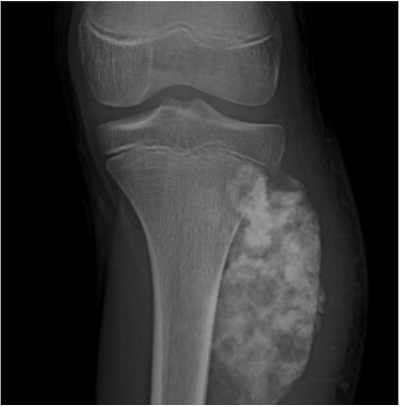

Kanker tulang merupakan jenis tumor tulang ganas yang berasal dari sel-sel tulang. Kanker ini dapat terjadi pada bagian tulang manapun pada tubuh manusia, paling sering terjadi pada tulang panjang dan dekat dengan sendi lutut, panggul, dan bahu.

Osteosarcoma adalah sejenis kanker tulang primer terbanyak. Kanker tulang jenis ini berkembang di sel tulang lengan tungkai dan panggul, paling sering terjadi pada anak-anak dan remaja. Oleh karena itu, penting untuk juga memperhatikan kesehatan anak-anak dan remaja.

- Pemeriksaan Radiologi dengan foto rontgen, MRI, CT-Scan